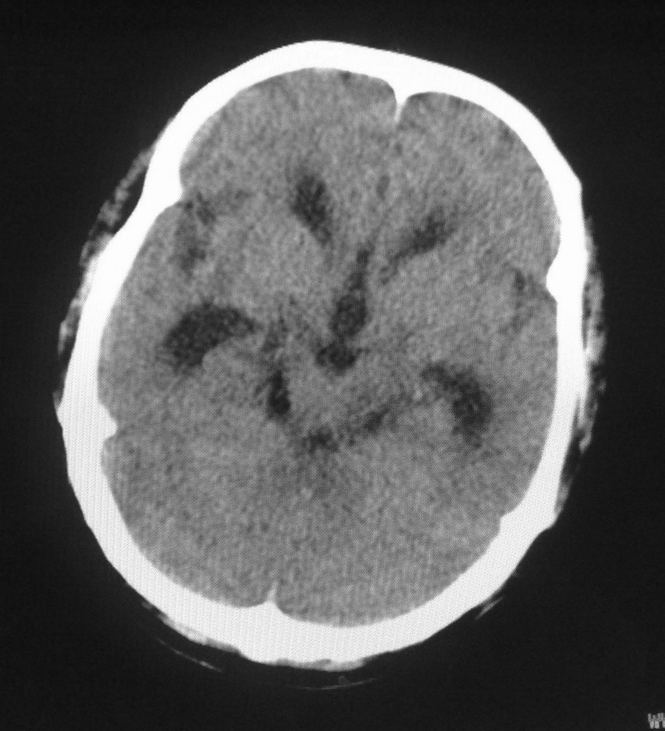

男,61岁,发热,有脑出血病史。

右侧基底节,放射冠软化灶,胼胝体发育不良 脑积水原因待查。

右侧基底节及放射冠软化灶,脑积水,四脑室显示不清,导水管梗阻?建议mri!

1)右侧基底节区、右侧放射冠及右侧丘脑软化灶。2)脑积水。